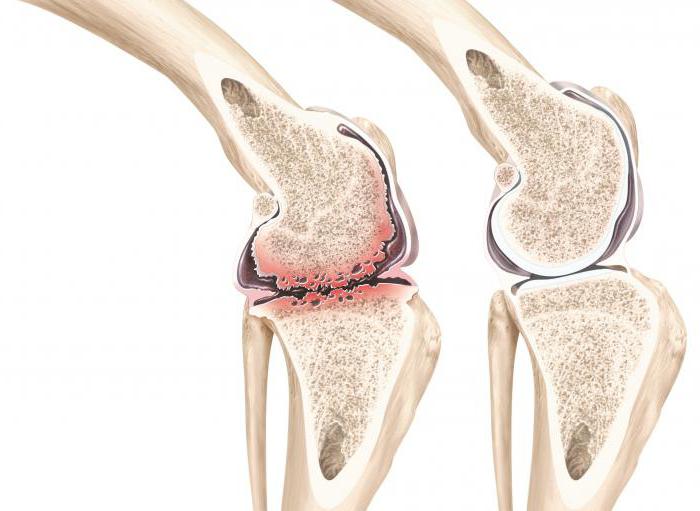

Медицинские состояния: Септический артрит коленного сустава